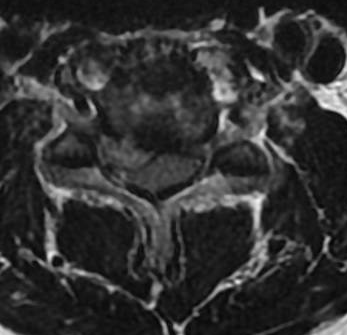

Case 1, Part 2: The patient had a #Vertiflex procedure done elsewhere; symptoms worsened, now can't stand upright, uses walker. Thoughts on her treatment so far? Next steps? #MedTwitter #Orthopedics #orthopedicsurgery #neurosurgery #spine #spinehealth #spinesurgery #scoliosis

55F with back pain and neurogenic claudication. Despite PT and epidural injections, relief is temporary. Difficulty walking long distances due to pain. What treatment would you offer next? #MedTwitter #SpineHealth #NeurogenicClaudication #spine